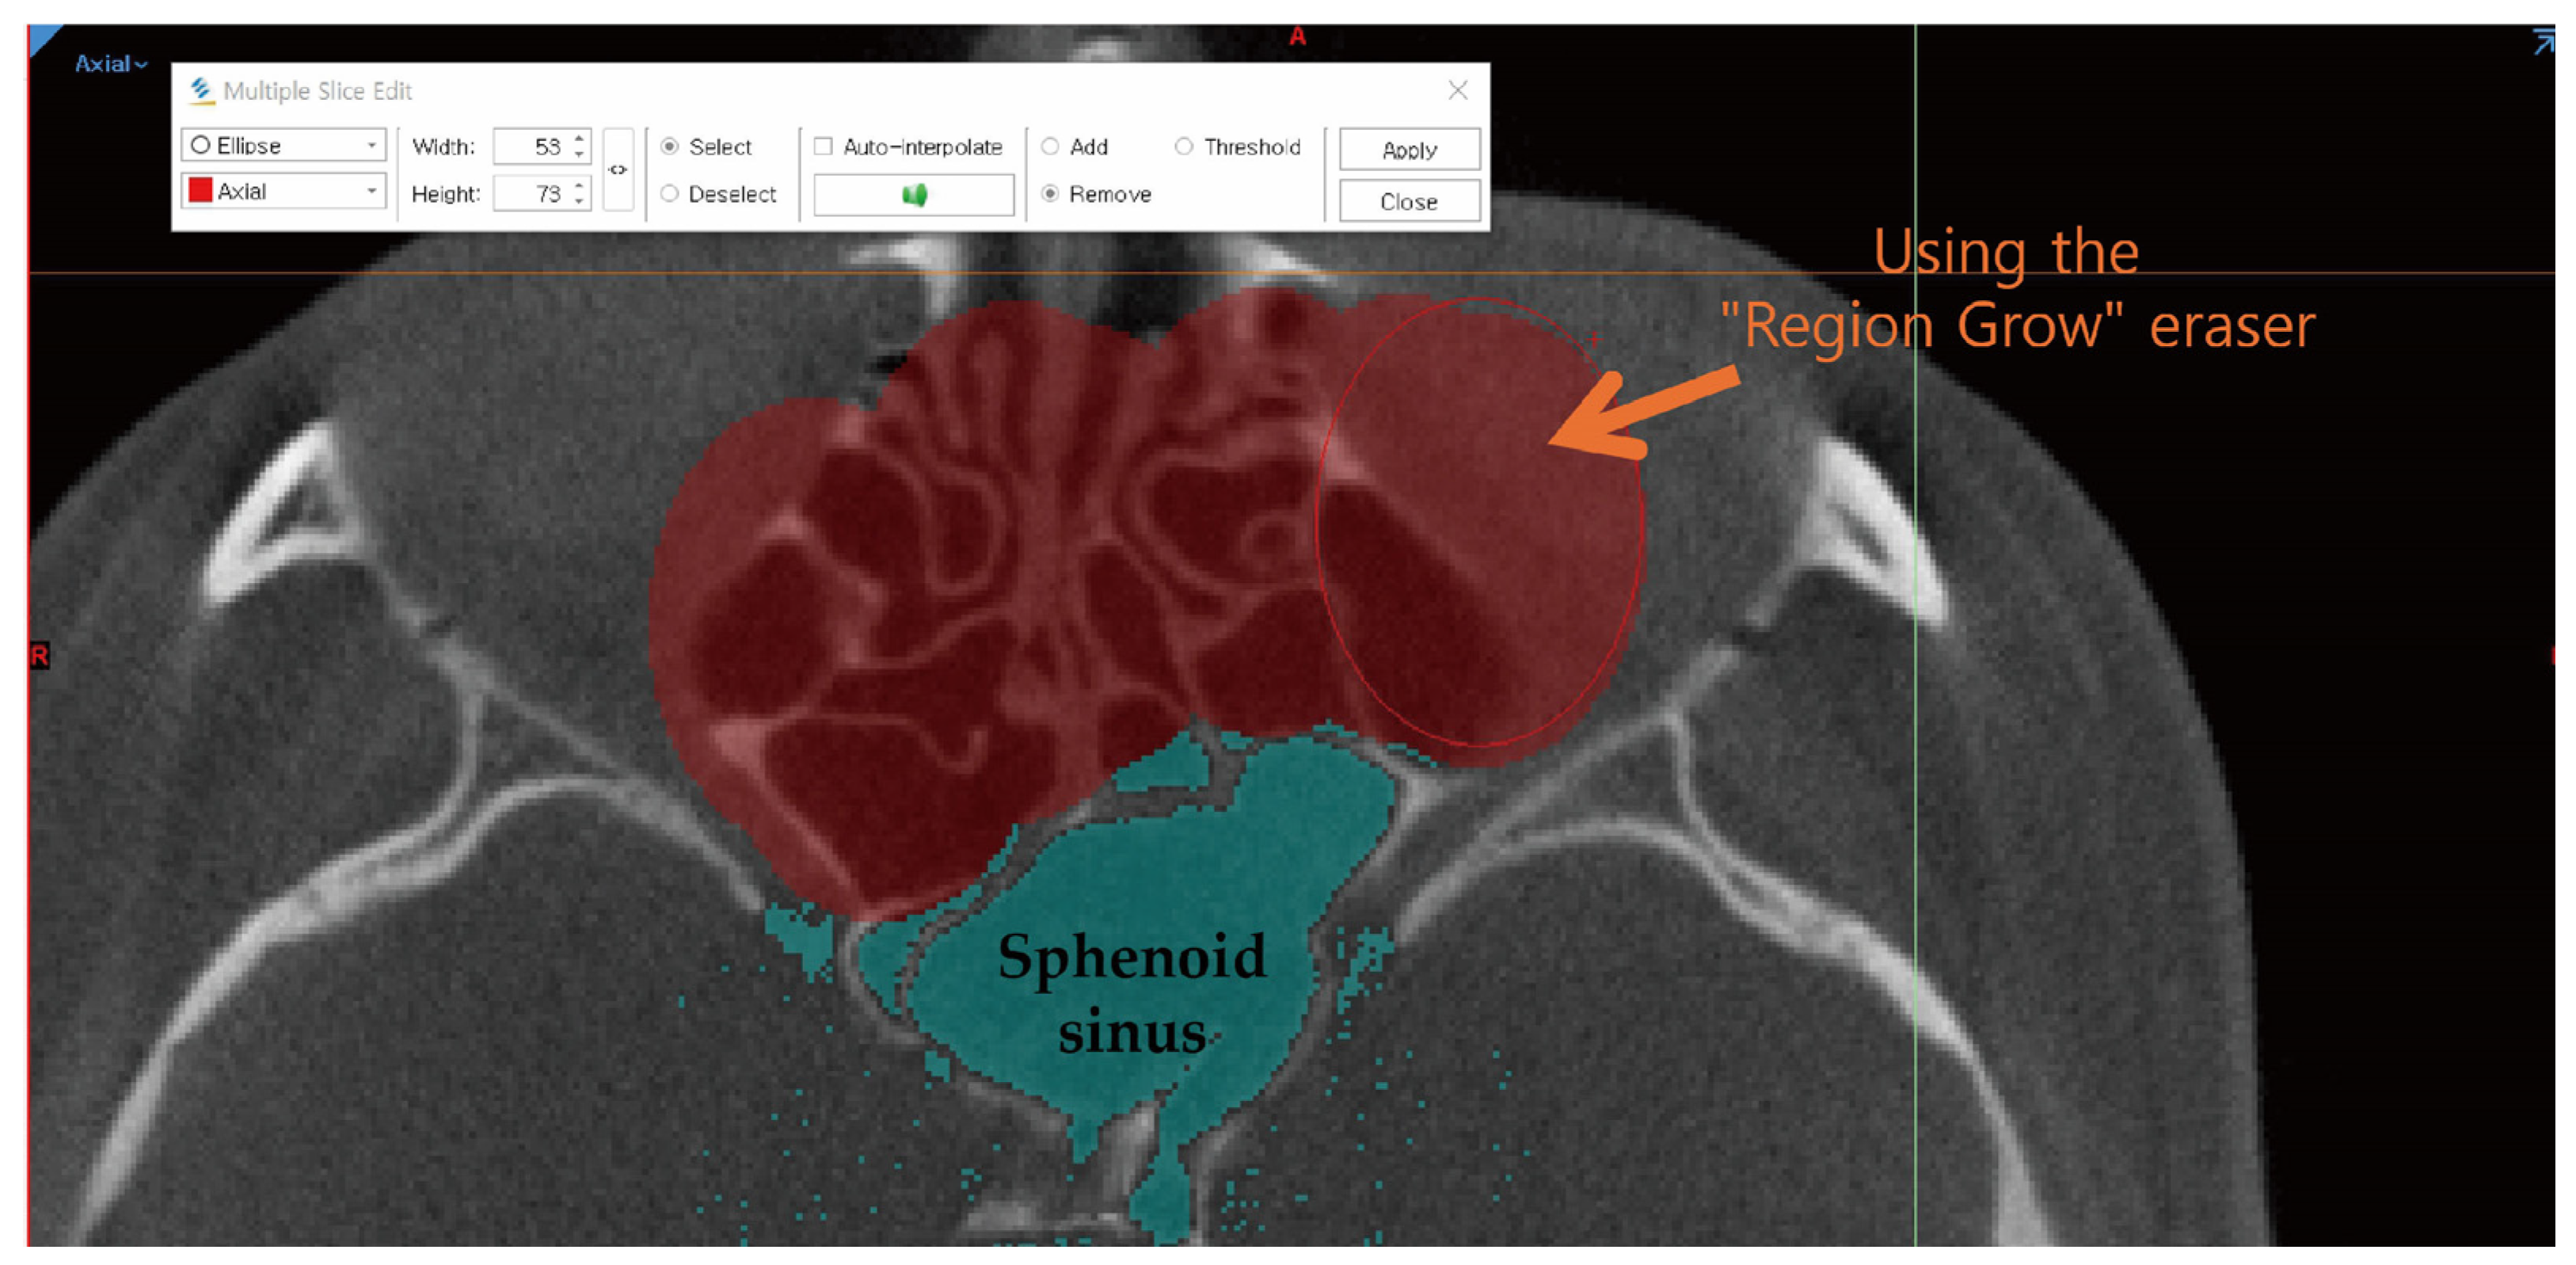

- Manual Editing and Cropping

- 3.

- Cross-sectional Validation